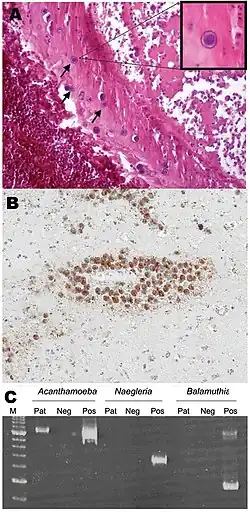

Granulomatous amoebic encephalitis (GAE) is caused by amoebic infection of the central nervous system (CNS). It is characterized by neurological symptoms including headache, seizures, and mental-status abnormalities.[1] These worsen progressively over weeks to months, leading to death in most patients.[1] Infection is generally associated with underlying conditions such as immunodeficiency, diabetes, malignancies, malnutrition, systemic lupus erythematosus, and alcoholism.[1] The parasite enters the body through cuts in the skin or by being inhaled into the upper respiratory tract.[1] The parasite then spreads through the blood into the CNS. Acanthamoeba crosses the blood–brain barrier by means that are not yet understood. Subsequent invasion of the connective tissue and induction of pro-inflammatory responses leads to neuronal damage that can be fatal within days. Pure granulomatous lesions are rare in patients with AIDS and other related immunodeficiency states, as the patients do not have adequate numbers of CD+ve T-cells to mount a granulomatous response to Acanthamoeba infection in CNS and other organs and tissues.[4] A perivascular cuffing with amoebae in necrotic tissue is usual finding in the AIDS and related T-cell immunodeficiency conditions.

Brain biopsy normally reveals severe oedema and hemorrhagic necrosis.[7] A patient who has contracted this illness usually displays subacute symptoms, including altered mental status, headaches, fever, neck stiffness, seizures, and focal neurological signs (such as cranial nerve palsies and coma), all leading to death within one week to several months.[8] Due to the rarity of this parasite and a lack of knowledge, no good diagnoses or treatments for Acanthamoeba infection are now known. Acanthamoeba keratitis cases in the past have resolved from a therapy consisting of atropine and some other drugs with no antimicrobial effects. Recent publications show atropine to interfere with the protist's CHRM1 receptor, causing cell death.[9]

Infection usually mimics that of bacterial leptomeningitis, tuberculous meningitis, or viral encephalitis. The misdiagnosis often leads to erroneous, ineffective treatment. In the case that the Acanthamoeba is diagnosed correctly, the current treatments, such as amphotericin B, rifampicin, trimethoprim-sulfamethoxazole, ketoconazole, fluconazole, sulfadiazine, or albendazole, are only tentatively successful. Correct and timely diagnosis, as well as improved treatment methods and an understanding of the parasite, are important factors in improving the outcome of infection by Acanthamoeba. A paper published in 2013 has shown substantial effects of some FDA-approved drugs with an in vitro kill rate above 90%.[4] These results were in vitro effects, but as the drugs are already approved, human infections can be targeted after dose calculations in clinical trials done with these diverse groups of drugs.